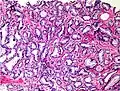

Gleason score 6 (3+3)

Cribriform pattern: Gleason grade 4

Gleason 3

Gleason 3 is a clearly infiltrative neoplasm, with extension into adjacent healthy prostate tissue. The glands alternate in size and shape, and are often long/angular. They are usually small/micro-glandular in comparison to Gleason 1 or 2 grades. However, some may be medium to large in size. The small glands of Gleason 3, in comparison to the small and poorly defined glands of pattern 4, are distinct glandular units. Mentally you could draw a circle around each of the glandular units in Gleason 3.[4][7]